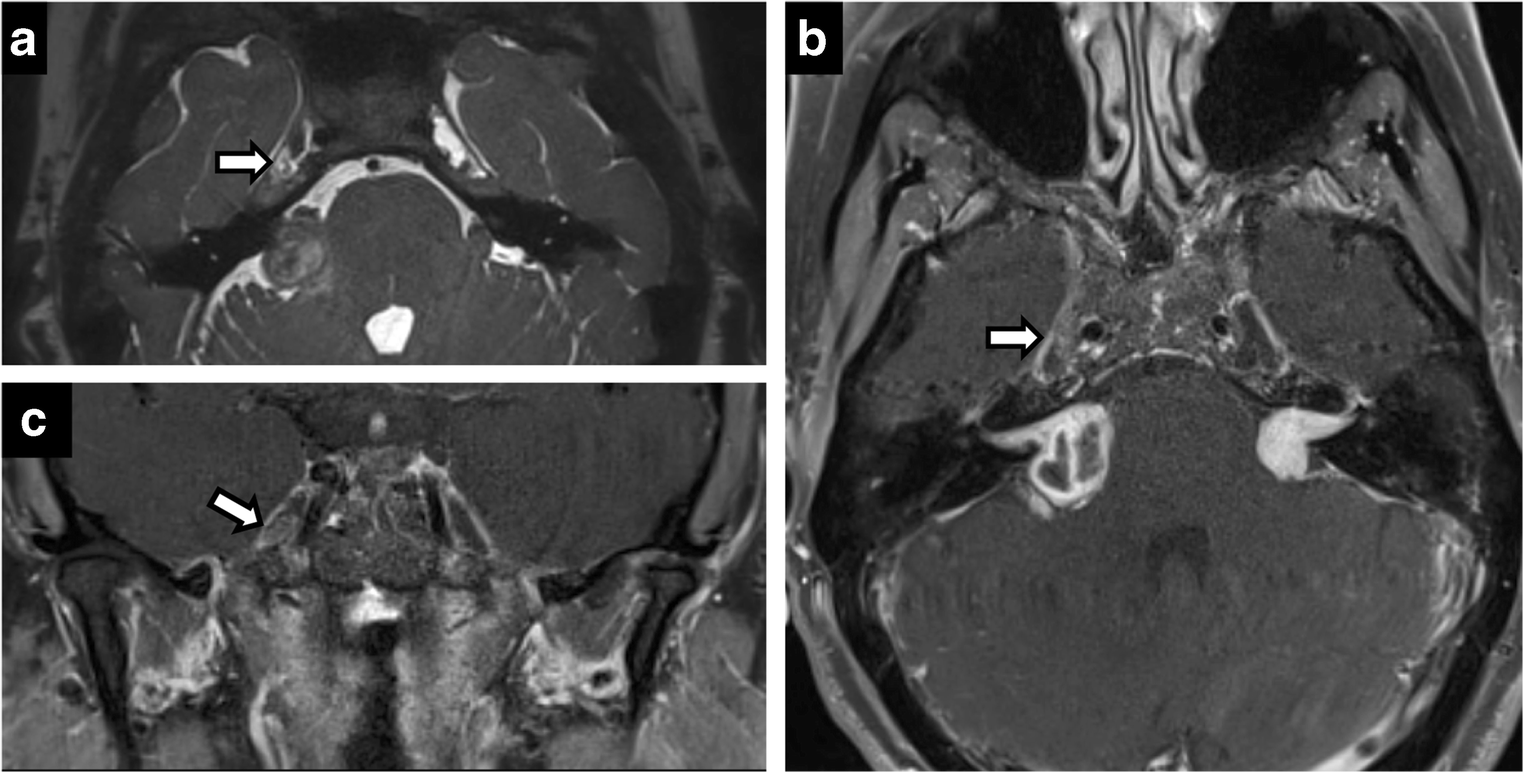

Neuroimaging of Meckel’s cave in normal and disease conditions Where Is Meckel's Cave Located trigeminal cave, also known as meckel’s cave or the trigeminal impression, is a depression on the front surface of the. The trigeminal ganglion lies in a space near the top of the temporal bone, on the inside of the skull,. Where Is Meckel's Cave Located.

Neuroimaging of Meckel’s cave in normal and disease conditions Where Is Meckel's Cave Located The trigeminal ganglion lies in a space near the top of the temporal bone, on the inside of the skull,. trigeminal cave, also known as meckel’s cave or the trigeminal impression, is a depression on the front surface of the. Where Is Meckel's Cave Located.